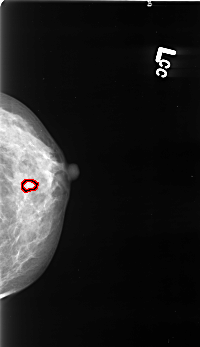

B_3418_1.LEFT_CC

LEFT_CC LINES 4504 PIXELS_PER_LINE 2600 BITS_PER_PIXEL 12 RESOLUTION 50 OVERLAY

FILE: B_3418_1.LEFT_CC.OVERLAY

TOTAL_ABNORMALITIES 1

ABNORMALITY 1

LESION_TYPE CALCIFICATION TYPE PUNCTATE-AMORPHOUS DISTRIBUTION CLUSTERED-LINEAR

ASSESSMENT 4

SUBTLETY 3

PATHOLOGY BENIGN

TOTAL_OUTLINES 1

BOUNDARY